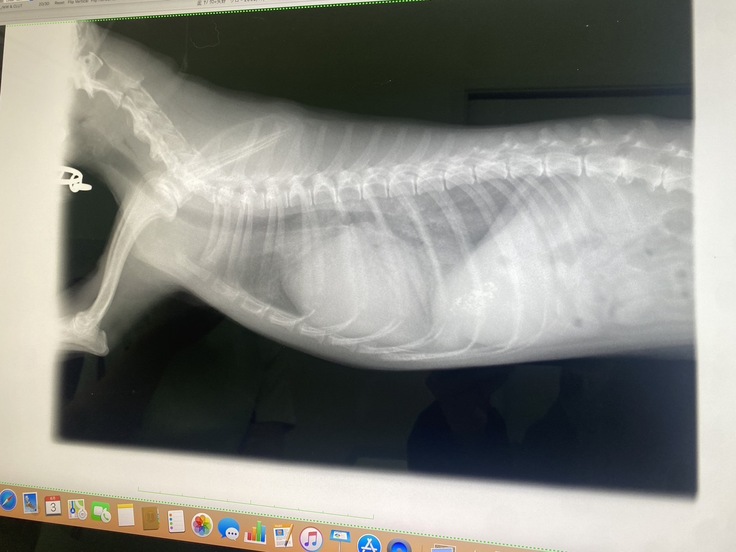

深夜救急に駆け込んだものの、病院についてのエコー・レントゲン・血液検査の結果では肺水腫の兆候は見られず…。

↑深夜救急では異常のなかった胸部が、白くなっています。